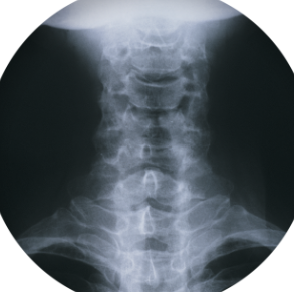

목 디스크에 좋은 운동 총 정리 알아보아요 목 디스크에 좋은 운동에 대해 알아보도록 하겠습니다. 목 디스크란 목뼈 사이에 있는 추간판이 튀어나와 신경을 압박하거나 자극하는 질환입니다. 목 디스크는 교통사고, 외상, 퇴행성 변화 등의 원인으로 발생할 수 있으며, 초기에는 증상이 뚜렷하지 않을 수 있습니다.